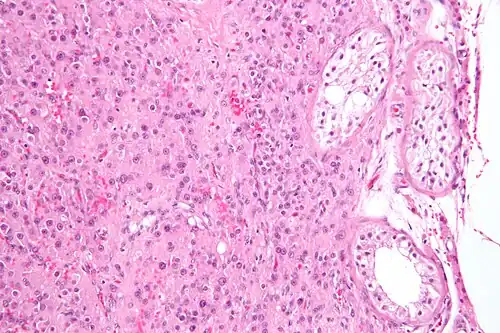

| Histopathology of a Leydig cell tumor, high magnification, H&E stain, showing typical features.[1] | |

A conclusive diagnosis is made via histology, as part of a pathology report made during or after surgery. Reinke crystals are classically found in these tumours and help confirm the diagnosis, although they are seen in less than half of all Leydig cell tumours. Immunohistochemical markers of Leydig cell tumours include inhibin-alpha, calretinin, and melan-A.[9]